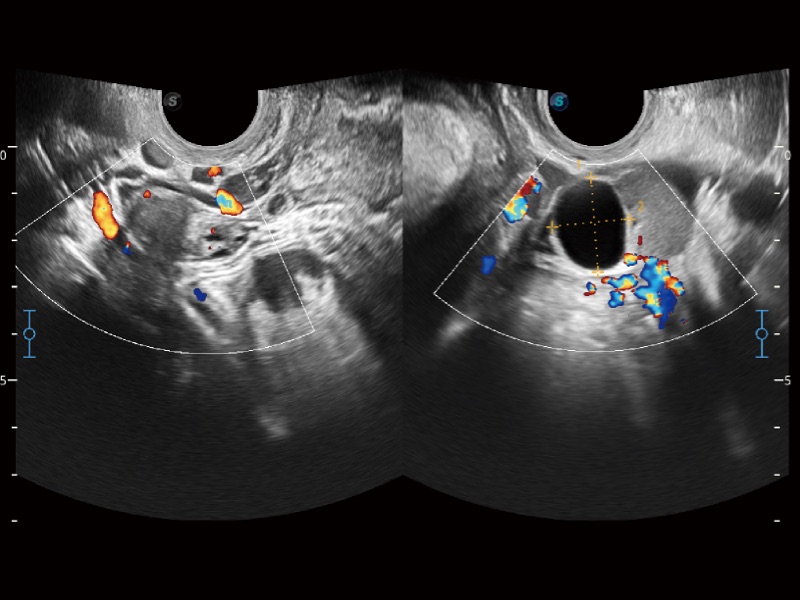

小器官应用

高分辨率血流成像技术提高了对低速血流信号的检测能力。在提高空间分辨率的同时,也克服了血流外溢现象,为用户提供更加真实的血流动力学信息。